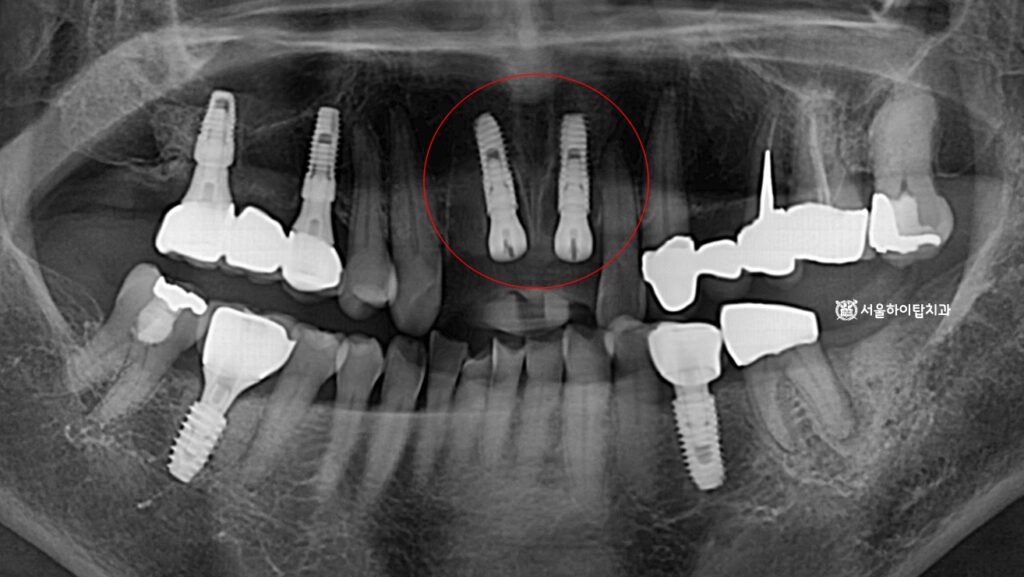

3. 수술 완료

시뮬레이션에 따라

정확한 위치이 안전하게

픽스처각 심겨진 모습입니다.

사진을 보면 두 개의 픽스처만

식립된 것을 확인할 수 있는데,

이는 전치부에 해부학적 구조와

골 형태를 고려한 결과입니다.

치조골 폭이 좁고, 치은라인이

중요한 부위이기 때문에

불필요하게 많은 임플란트를 심기보다는

기능 안정성과 심미 조화를 동시에

확보할 수 있는 최소 개수를

선택하는 것이 원칙입니다.

만수동 치과 에서 남은 한 자리는

폰틱(가짜치아)으로

대체될 것으로 보입니다.